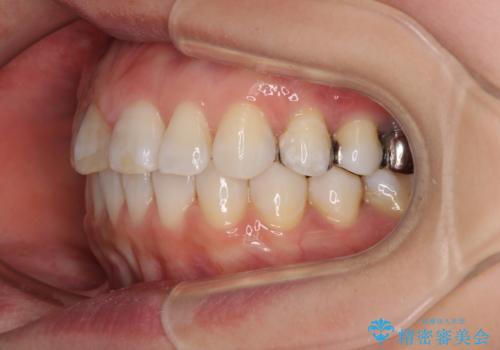

- 前歯のデコボコを治したいとのことで来院された患者様です。

上下顎ともに歯列全体の後方移動とIPR(歯と歯の間を削る)によってデコボコが解消するように設計し、インビザラインにより治療を行うこととしました。

しっかりと装着時間を守ってくださったのですが、途中妊娠にともなう悪阻や出産といったイベントがあり、予定よりも治療期間が長くなりました。